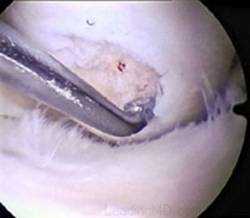

Chirurgul trebuie sa fie foarte atent atunci cand examineaza posteriorul condililor femurali. Daca se semnaleaza orice vatamare/rana/deteriorare pe suprafetele articulare, trebuie sa se cerceteze atent calitatea cartilagiului. Orice flapsuri instabile sunt inlaturate prin folosirea unui aparat de ras electric artroscopic sau curette. Apoi, un curette este folosit pentru a debrida stratul de cartilagiu calcifiat de la baza in toata grosimea defectului. Acest pas se bazeaza pe activitatea lui Frisbi, care a demonstrat vindecarea suprafetei articulare superioare la un cal, cand stratul cartilagiului calcifiat este indepartat. Cand indepartam stratul cartilagiului calcifiat, in general nu se foloseste un aparat de ras. Cu un aparat de ras este dificil de controlat cantitatea de os eliminat, si este posibil ca osul subcondral sa fie afectat.

Dupa indepartarea cu succes a stratului de cartilaj calcifiat, o andrea este folosita pentru a face mai multe gauri mici (mirofracturi) in osul expus al defectului condral aflate la distanta de 1-2 mm. Trebuie lasata o punte de oase potrivita intre gauri. Tehnica de microfracturi are numeroase avantaje fata de foraj. Mai intai de toate, creaza o leziune termala mai mica. Mai mult, cu microfracturi, chirurgul este capabil sa intre in zonele dificile ale suprafetei articulare cu un control mai bun asupra adancimii de patrundere. La finalizarea microfracturii, o suprafata aspra este generata pentru a aderenta cheagului de sange care contine celule mezenchimale nediferentiate de la osul subcondral. Trebuie avut grija ca cele mai marginase parti ale leziuni sa fie patrunse de andrea pentru a ajuta la vindecarea tesutului reparator la imprejmuirea suprafetei articulare. Odata ce microfractura este finalizata, pompa artroscopica este oprita pentru a se asigura ca sangerarea maduvei curge din gaurile mici umpland defectul.[54]

Andrelele de microfracturare cu unghi reglabil actioneaza moderat astfel incat gaurile verticale pot fi facute fara daune termice. Se fac gauri chiar de la marginea defectului.

Artroscopia arata repararea tesuturilor la sase saptamani.